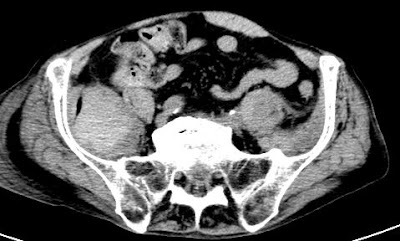

NECT shows spontaneous hyperdensity (55-60 HU) in the swollen iliacus muscle

Typical localisation of intramuscular bleeding in elderly patients.

Other frequent localisations: psoas muscle, abdominal wall, quadriceps femoris muscle.